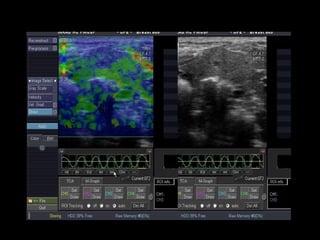

Modo B,  Modo Parametric Image (colorido) e gráfico Cm 2  Histogram . Neste exemplo, observa-se imagem no modo parametric image, áreas de fibrose (em vermelho e amarelo), que refletem a curva em azul no modo Cm histogram, de aspecto irregular, compatível com fibrose.